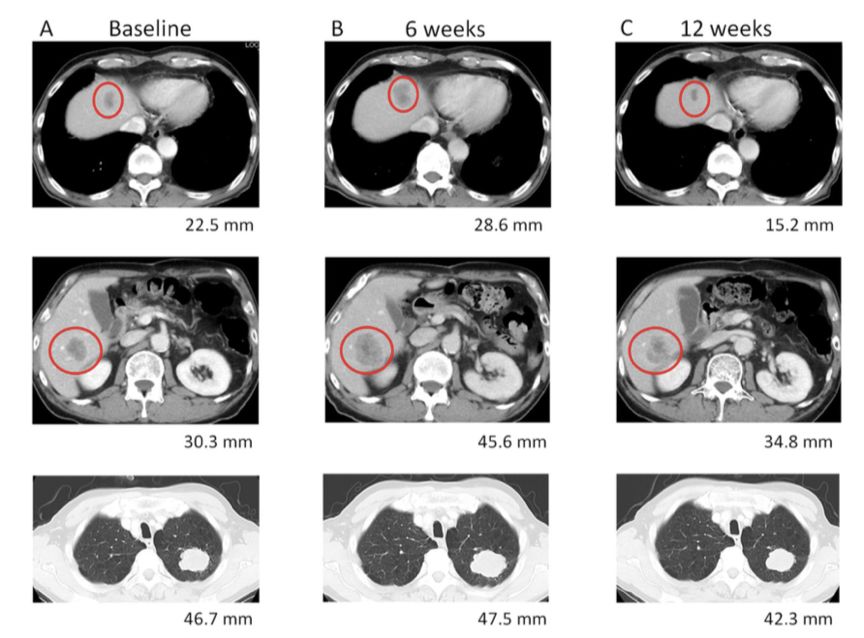

图1. 患者初诊(A)、纳武利尤单抗治疗6周(B)肝转移灶和肺原发灶的CT影像

图3. 患者初诊(A)、纳武利尤单抗治疗6周(B)、纳武利尤单抗治疗12周(C)肝转移灶和肺原发灶的CT影像